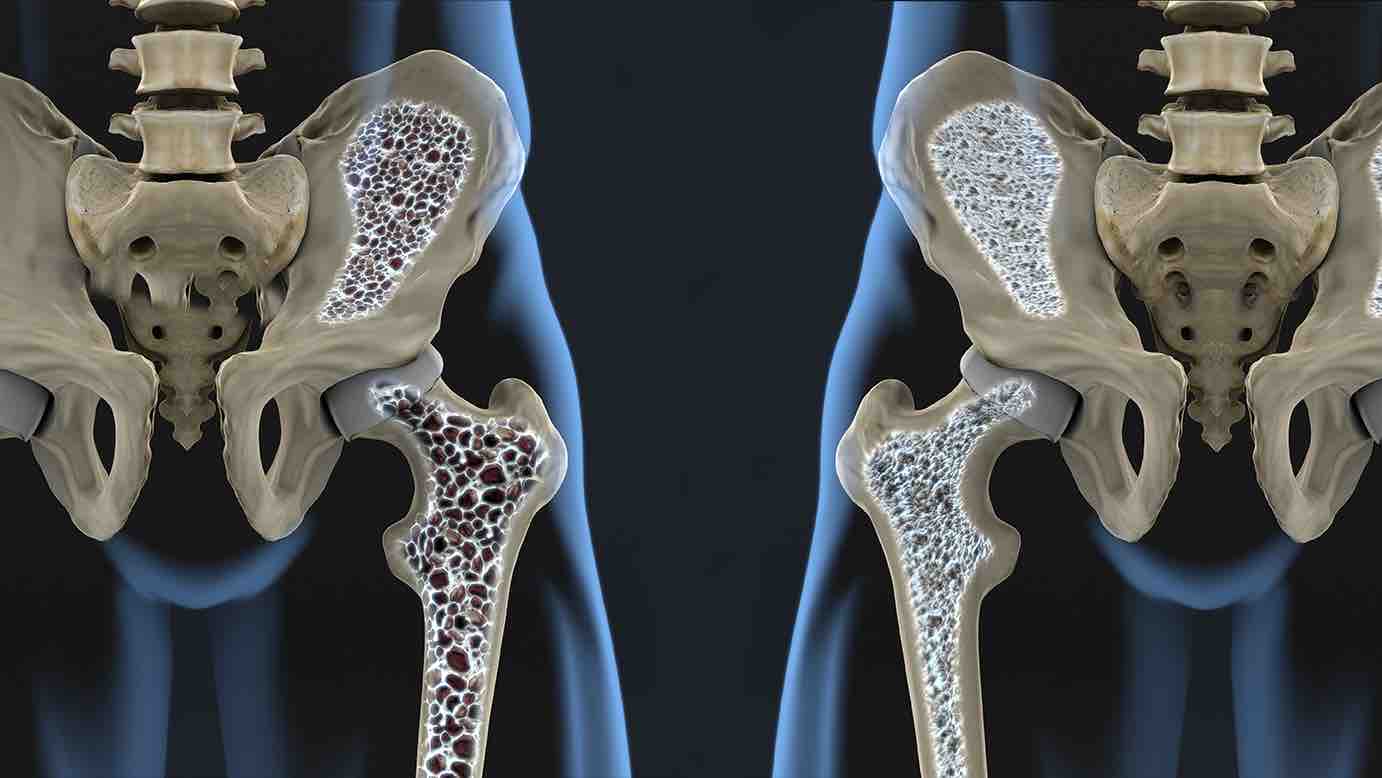

La osteoporosis, una condición que debilita los huesos y aumenta el riesgo de fracturas por fragilidad, representa un desafío significativo para los pacientes y el sistema de salud. Tras una fractura, el riesgo de sufrir una nueva fractura se multiplica por cinco, lo que subraya la importancia de un tratamiento eficaz y un seguimiento riguroso.